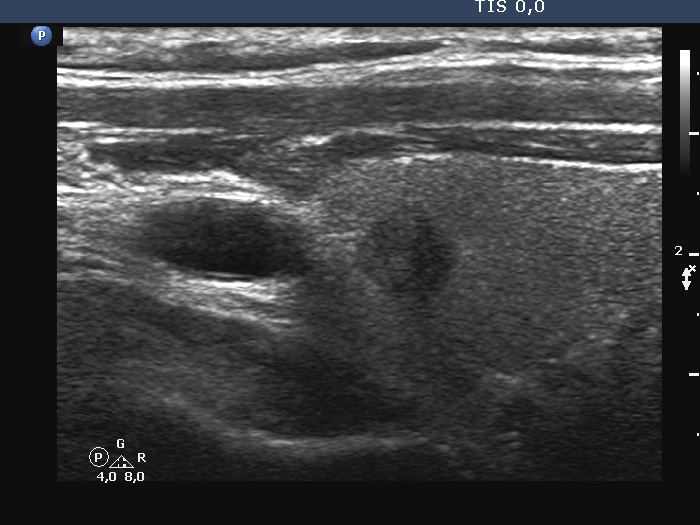

Ultrasonography. The thyroid was echonormal. There was a hypoechoic lesion in the right lobe. The lesion presented irregular borders and no vascularity. The size of the nodule was 7x6x8 mm, width, depth, length, respectively.

It is worth comparing the test performed at a higher and lower frequency. It's not just obesity, it can worsen image quality (the patient had an average build). In men, probably the different consistency of connective tissue and/or muscle tissue often impairs the penetration of ultrasound.

The absolute measure of surface irregularities was not high, however, it is worth comparing the degree of undulations to the size of the nodule. I regard this as pathological lobulation.